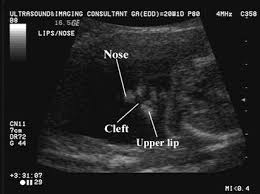

I may just be being paranoid bc i am a very paranoid person anyway. Involve the superficial tissues. Cleft lip may be detected with ultrasound beginning around the 13th week of pregnancy. Best seen on coronal images of the upper lip.

Best seen on coronal images of the upper lip. Type 2 unilateral. My ultrasound tech said that she can easily spot a cleft lip but a cleft palate is much harder to see i am sure you could google ultrasound pics with cleft lips and see some pictures. An explanation why the cleft was mistakenly considered to be one on the left side could be that the cleft was located near to the midline and the 2d ultrasound frontal view was an oblique frontal view figure 1.

Midline sagittal views normal. Ultrasound pic looks like cleft lip and im freaking out. Ultrasound of cleft lip and palate. What does cleft lip look like in ultrasound i think you can see it easily especially the 3d 4d one.